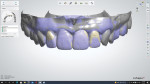

The technician poured the model and scanned it for digital design of the final restorations (Figure 3 and Figure 4). The milled restorations (Figure 5) were designed with built-in surface characterizations executed by the mill (PrograMill PM7, Ivoclar Vivadent). Prior to sintering, the technician used an infiltration technique to obtain OM2 shade by infiltrating IPS e.max ZirCAD Prime BL2 shade with the IPS e.max ZirCAD LT B1 Liquid. This technique saved 1 hour of time in comparison to the traditional staining and firing technique. With the application of tooth shade OM2 coloring liquid to the unsintered restorations, the final esthetic appearance was achieved during the sintering phase (Figure 6 and Figure 7). The final restorations were seated on the model (Figure 8 and Figure 9) to check the fit.